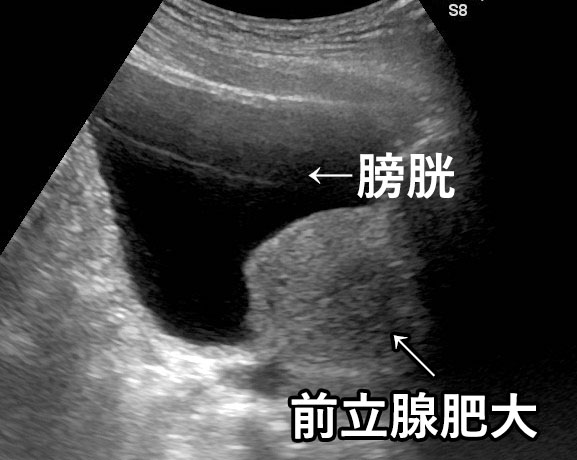

正常な前立腺のエコー画像

前⽴腺肥⼤症のエコー画像